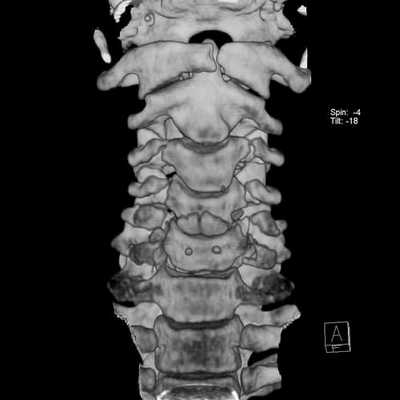

Перелом грудного отдела (трехмерная и сагиттальная проекции)

В результате компьютерной томографии получают серию послойных изображений рассматриваемой зоны. Монохромные фотографии обладают высоким разрешением. В отличие от рентгенографии на снимках отсутствуют дефекты и тени от расположенных рядом структур. Изменение плоскости при реконструкции изображений позволяет тщательно изучить анатомические образования. Преимуществом КТ является возможность создания 3D-модели позвоночника.

Трехмерная реконструкция при КТ